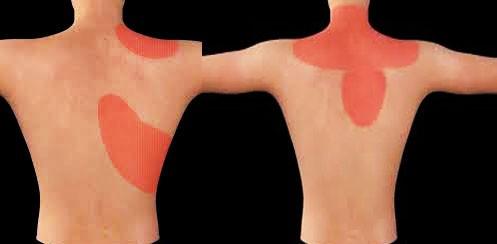

之所以把心梗诱发的肩痛写在最前面,是因为忽视这个问题可能导致非常严重的后果。很多朋友可能都知道发生心脏缺血、甚至心梗的时候,会有严重的胸痛,有的会伴有呼吸困难,大汗淋漓以及濒死感,但是可能有一些朋友比较忽略的是心肌梗死可能造成的症状就是肩膀疼痛、胃痛、牙痛和肩胛骨区域的疼痛。

尤其是一些患者,如果平时肩膀就不是特别的好,那么在发生心梗的时候,如果出现了肩膀的疼痛,可能就会因为平时有肩痛的毛病而忽视考虑存在心梗的可能,所以建议,有常年的高血压、冠心病、糖尿病的患者,又或者平时频繁的出现心绞痛,又或者最近特别的劳累,长时间的处于高压状态下,出现了肩膀的疼痛、胃区的不适、或者是牙周的疼痛,如果经过15~30分钟不缓解,甚至有越来越重的情况,很有可能是心肌在求救,请一定要考虑到有可能是心肌梗死,无论年纪多大,因为现在出现猝死的年龄段越来越年轻化了。

但有一部分的患者不仅表现为肝区、胆囊区的不适,还会表现为肩膀和背部的不适。

由胆囊诱发的肩部疼痛,往往有它的特点,如果是慢性胆囊炎症,往往疼痛并不是特别的严重,而且一般都是在进食比较油腻的食物以后出现疼痛。因为在进食大量脂肪的时候,胆囊会分泌胆汁刺激到胆囊,诱发疼痛。发生急性胆囊炎或者是因为急性的胆管梗阻造成胆道问题的时候,患者不仅会表现为疼痛,同时会表现为恶心,腹痛等症状,严重的患者甚至会出现发热、皮肤黄疸,所以由胆囊诱发的疼痛和肩关节疾病导致的疼痛还是有一些可以鉴别的地方。另外如果存在胆囊的炎症或者是胆石症,可以通过彩超检查来明确胆囊是否存在着问题。